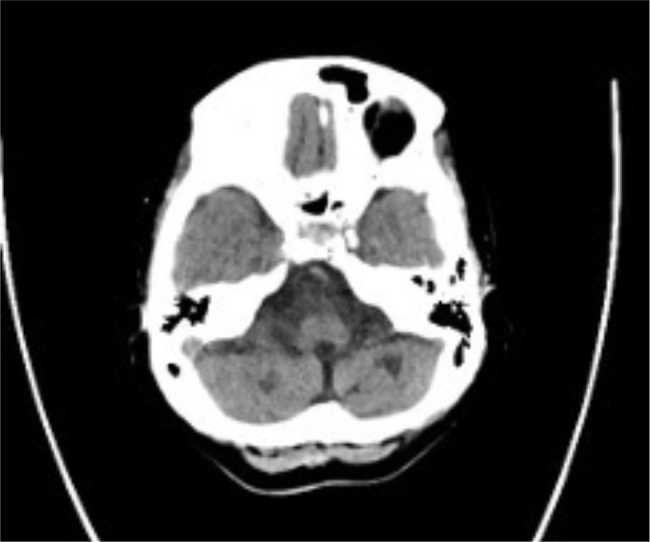

Case description: A 45-year-old female with diabetes, hypertension and multiple ischaemic strokes presented with altered consciousness due to hypoglycaemia. Initial workup at a different hospital suggested cerebral vasculitis based on the findings of cerebral angiography. She had negative systemic vasculitis markers and was treated with corticosteroids and rituximab and discharged. On admission to our facility, an MRI of the brain revealed multiple infarcts of varying ages, and a CTA showed arterial beading, suggestive of primary CNS vasculitis. CSF analysis demonstrated elevated protein and IgG without pleocytosis. Despite high-dose corticosteroids and rituximab, she developed progressive neurological deterioration with new infarcts in the vertebrobasilar territory, leading to brainstem dysfunction and brain death.

Learning points: Physicians should be alert in diagnosing primary CNS vasculitis in a young patient with recurrent strokes affecting multiple vascular territories, particularly when systemic vasculitis markers are negative.Imaging studies, such as MRI and computed tomography angiography (CTA), play an essential role in diagnosing primary CNS vasculitis, with findings such as arterial beading and a multi-infarct pattern helping differentiate it from atherosclerotic diseases.Early recognition and aggressive high-dose corticosteroid and immunosuppressive (rituximab) therapy are essential in primary CNS vasculitis, as delayed treatment can result in rapid neurological deterioration, as seen in this case.